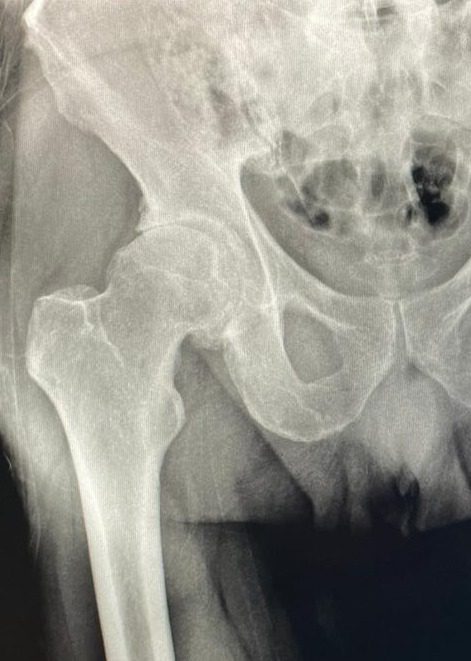

O que é Artrose do Quadril?

A artrose do quadril, ou coxartrose, é uma condição degenerativa que afeta a articulação do quadril, caracterizada pelo desgaste progressivo da cartilagem que reveste os ossos da articulação. Esse desgaste leva ao atrito entre os ossos, causando dor, rigidez e limitações de movimento.